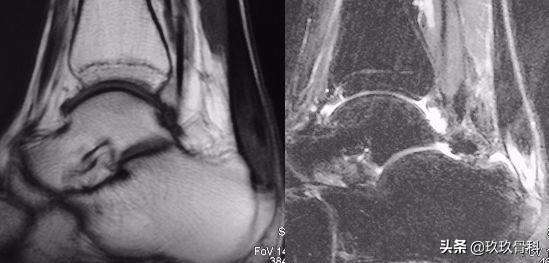

辅助检查

- MRI

- 合并距骨关节面的骨软骨切线骨折

- 关节软骨和骨软骨损伤